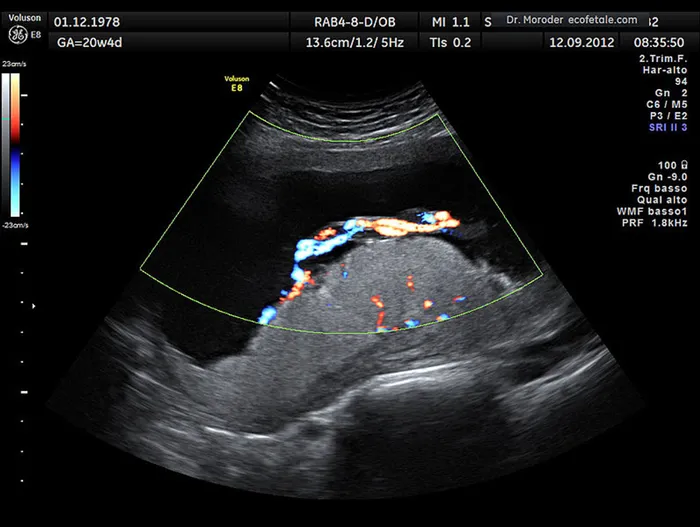

File photo: Twelve weeks into her pregnancy, she started spotting, and a scan at the University Hospital of North Durham revealed her suspected pregnancy was in fact cancer. Picture: Wikimedia Commons